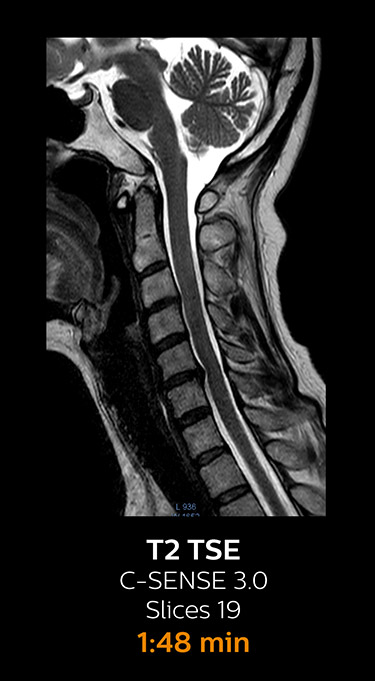

With Compressed SENSE, the scan time for the routine cervical spine examination at KNC was reduced from 13:11 to 9:52 minutes, which corresponds to 25% reduction.

MRI examination of the cervical spine with Compressed SENSE

Ingenia 3.0T CX

Scan time 9:52 min. (was 13:11 min. without Compressed SENSE)